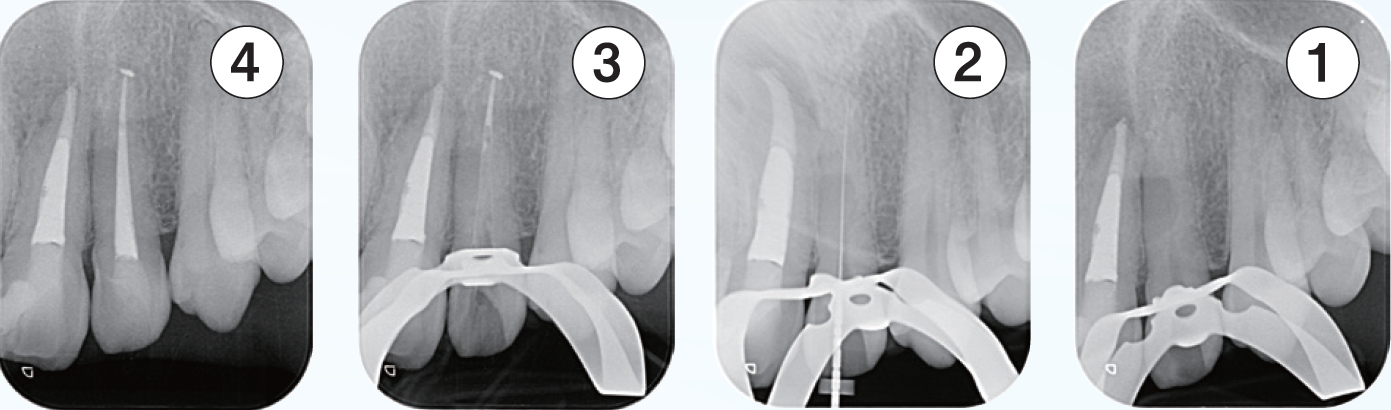

「臨床症例2」複雑な湾曲を有する根管に対して対処したケース

●年齢50代 男性

咬合による歯冠破折から歯髄炎になり、根管処置が必要となる。器具操作が困難なため、紹介を受け当院を受診。近心頬側根管は根管口付近は狭窄を呈し、遠心方向に向けて開口しており、近心頬側根管の器具の挿入はかなり遠心方向から器具を回し込む必要があった。また根尖の開口部は近心方向にあり、根管の全体的な形態はS字のような形態を有する。全体的に湾曲度を緩やかになるよう処置を進めた。器具の選択に関しては、より柔軟性のあるマルテンサイトのニッケルチタンファイルを選択した。根管口付近の形態修正は器具が歯軸に対して極力平行になるように行なった。EMR時のレントゲン像では、3根管それぞれが歯軸に対してほぼ平行に挿入されていることが確認できる。しかしながら根尖部付近がそれぞれ大小の湾曲を有し、特に近心頬側根は近心方向に湾曲している。根管上部の形態修正とマルテンサイトのファイルの使用によって根尖への器具の到達に成功した。根管充填はウォームドガッタパーチャとMTAシーラーを用いセクショナル法で行った。術後4年弱のレントゲン像で、根尖周囲の歯周組織は安定していることが確認できる。

① 初診時(2021/06/21)

口蓋根根尖部には炎症による歯根膜腔の拡大が見られる

②EMR測定時

根管口付近の修正形成を行い、ファイルが歯軸に対して平行に入ることによって根尖部の湾曲に対してニッケルチタンファイルがその特性を活かし、元々の根管形態を崩さず追従し根尖部への到達を獲得できている

③根管充填時

それぞれの根の根尖部に根管充填材が到達していることが確認できる

近心頬側根根管は根尖部は近心方向に湾曲して開口しているのが確認できる

④補綴装置装着時

根管処置後臨床症状もなくレントゲン所見も安定している

⑤術後4年弱(2025/05/28)

臨床症状もなく経過良好であり、初診時に見られた口蓋根根尖部の歯根膜腔の拡大も改善し安定している